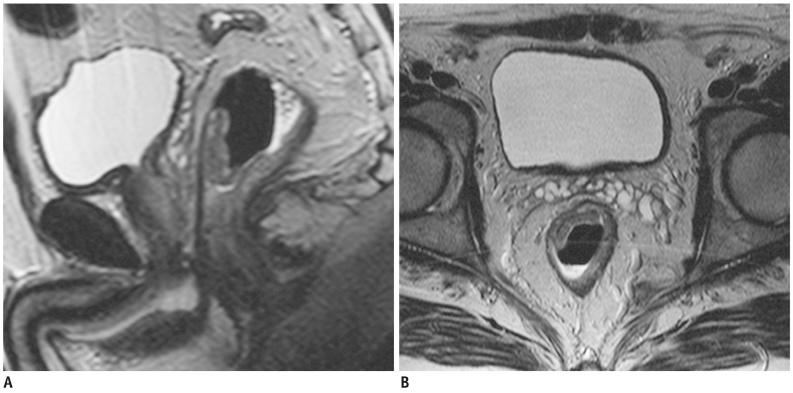

Seventy-three patients with primary rectal cancer underwent high-resolution MRI with a phased-array coil performed using 60-80 mL room air rectal distention, 1-3 weeks before surgery. MRI results were compared to postoperative histopathological findings. The overall MRI T staging accuracy was calculated. CRM involvement prediction and the N staging, the accuracy, sensitivity, specificity, positive predictive value (PPV) and negative predictive value (NPV) were assessed for each T stage. The agreement between MRI and histological results was assessed using weighted-kappa statistics.

The overall MRI accuracy for T staging was 93.6% (k = 0.85). The accuracy, sensitivity, specificity, PPV and NPV for each T stage were as follows: 91.8%, 86.2%, 95.5%, 92.6% and 91.3% for the group ≤ T2; 90.4%, 94.6%, 86.1%, 87.5% and 94% for T3; 98,6%, 85.7%, 100%, 100% and 98.5% for T4, respectively. The predictive CRM accuracy was 94.5% (k = 0.86); the sensitivity, specificity, PPV and NPV were 89.5%, 96.3%, 89.5%, and 96.3% respectively. The N staging accuracy was 68.49% (k = 0.4).

MRI performed with rectal lumen distention has proved to be an effective technique both for rectal cancer staging and involved CRM predicting.